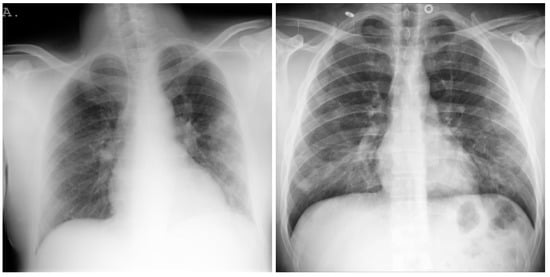

3.1. COVID-19 Image Data Collection (CIDC)

3.2. COVID-19 Radiography

3.3. BIMCV COVID19+

3.4. RSNA

3.5. Chest X-ray Images Pneumonia (CXRIP)